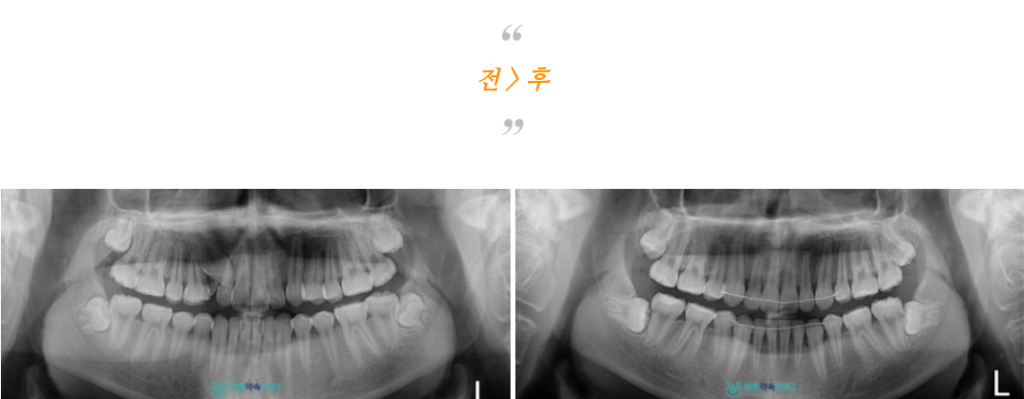

치료 마무리 후

위턱 오른쪽 견치가

제 위치에 바르게 자리 잡고

치열이 개선된 모습의

구강 내 모습과 파노라마 사진인데요.